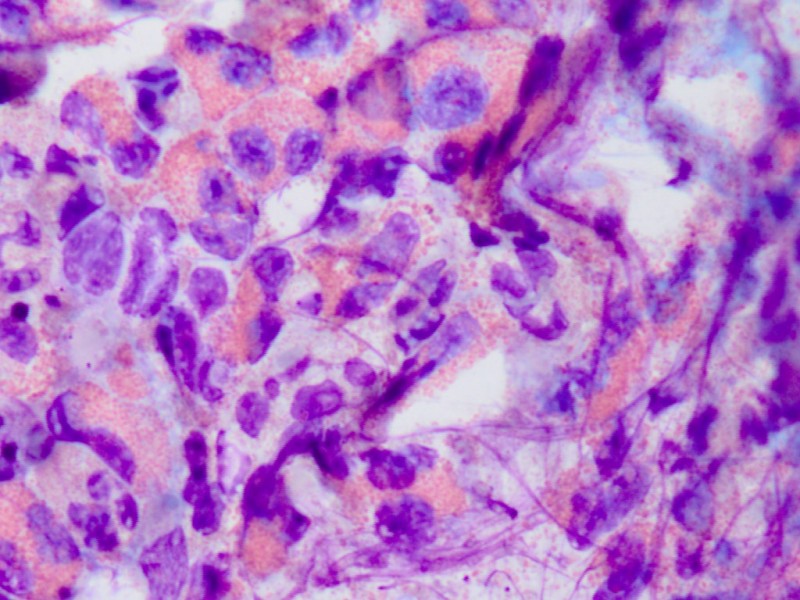

Diagnostiek:Inhoud van de pustel op een objectglas

uitsmeren en kleuren met een snelkleuring (b.v.

Diff-Quick kleuring). Sommigen noemen dit

een

Tzanck test, maar die naam is eigenlijk

gekoppeld aan het zoeken naar multinucleate cellen bij Herpes. Beoordeel of

er een puur eosinofiel infiltraat in zit, kijk ook naar de aanwezigheid van

veel bacteriën en neutrofiele granulocyten (banale folliculitis) of meerdere

Pityrosporum gisten (

Pityrosporum

folliculitis, Malassezia furfur). Zonodig een kweek van een pustel op bacteriën

![Diff-Quick preparaat met eosinofielen (click on photo to enlarge) [source: www.huidziekten.nl] Diff-Quick preparaat met eosinofielen](../../../images/eosinofielefolliculitissmear1z.jpg) |

![Diff-Quick preparaat met eosinofielen (click on photo to enlarge) [source: www.huidziekten.nl] Diff-Quick preparaat met eosinofielen](../../../images/eosinofielefolliculitissmear2z.jpg) |

| smear

met eosinofielen |

smear

![Diff-Quick preparaat met eosinofielen (click on photo to enlarge) [source: www.huidziekten.nl] Diff-Quick preparaat met eosinofielen](../../../images/eosinofielefolliculitissmear3z.jpg) |

![Diff-Quick preparaat met eosinofielen (click on photo to enlarge) [source: www.huidziekten.nl] Diff-Quick preparaat met eosinofielen](../../../images/eosinofielefolliculitissmear4z.jpg) |

met eosinofiele granula |

eo's en

Pityrosporum spp. |